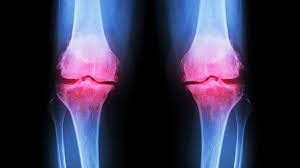

Osteoarthritis is a chronic arthropathy (A disease of the joint) characterized by the degeneration of cartilage and also by hypertrophy (increase in bulk as by thickening of the muscle fibers) of the bones and articular axis.

In osteoarthritis, there is minimum inflammation and the mechanical factors involved in its pathogenesis may vary.

The primary target here is the cartilage, cartilage damage should be discovered, swellings, pains, etc.

1. Destroying of the cartilage

2. Sclerosis: This is a pathological condition in which the cartilaginous tissues become very hard due to overgrowth of fibrous tissues or interstitial tissues and other changes.

3. Osteocytes pore formation: Formation of osteocytes in the cells of the bones can lead to weakened bones and bone fracture.

6. Joint narrowing due to the increase in swelling.